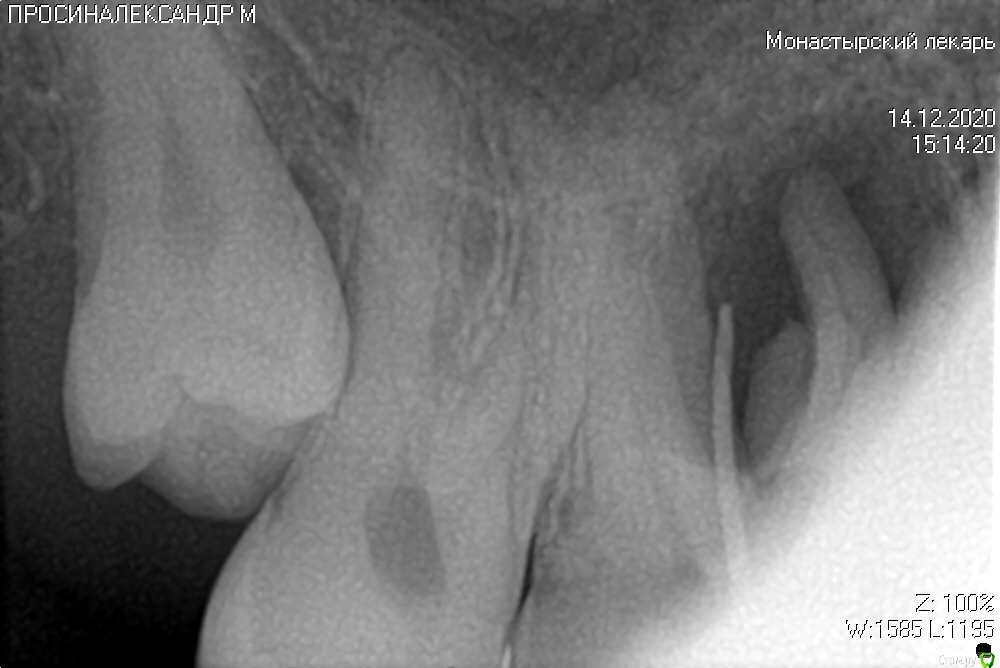

ромашечка Опубликовано 14 декабря, 2020 Поделиться Опубликовано 14 декабря, 2020 (изменено) Добрый день. Может что умного подскажите.Пациент 35 лет. КПУ 3. 15 зуб полностью разрушен. Занимает небное положение, вне зубного ряда..На слизистой оболочке щечно в проекции корней 16 зуба - свищ, гнойное отделяемое. 16 - с небольшой кариозной полостью. в цвете не изменен , подвижность отсутствует. Дриль тест резко болезнено. Тест на холод спрей +. 14 интактный, реакция на холод +, подвижность-, перкуссия - На Кт ( к сожалению только снимок какой есть с гутой в свище, не успела нафотографировать скрины) - "киста"-гранулема до 2 см в диаметре. небный корень 14 , медиальный и небный корни 16 плюс бифуркация в "кисте". Вердикт одного хирурга- удалять все. Второго- депульпировать 16 и 14. Мой- удалять 15 . И наблюдать . Контроль жизненспособности 16,14 после удаления ревизии в ранние сроки ,рентген кт попозже . Не права? Изменено 14 декабря, 2020 пользователем ромашечка 1 1 Ссылка на комментарий

ромашечка Опубликовано 14 декабря, 2020 Автор Поделиться Опубликовано 14 декабря, 2020 (изменено) Не обидите. 15 полностью разрушен, написано. На удаление. Второй эсперт тоже хирург. Прислал мне депульпировать 14,16 перед удалением 15 с "кистой". У меня не поднялась рука. Просто полечила кариес 16 . Данные понятно что надо Кт. Но пациент убежал к хирургу с диском . Обещал вернуться). Из анамнеза. Зуб разрушился около года назад. Никак не беспокоил. Неделю назад заболело, подпухла десна, появился свищ, боль прошла. Сделал кт . Пошел по хирургам. Изменено 14 декабря, 2020 пользователем ромашечка Ссылка на комментарий